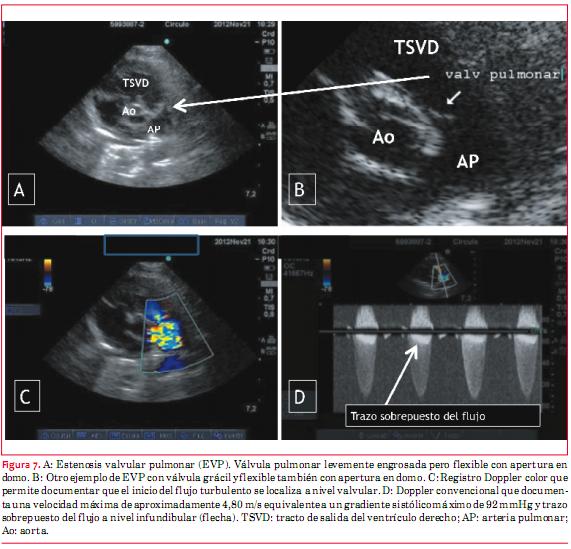

3. Estenosis pulmonar

La estenosis pulmonar (EP) puede ser subvalvular, valvular o supravalvular. Abordaremos aquí únicamente la estenosis valvular pulmonar. El diagnóstico ecocardiográfico de estenosis valvular pulmonar (figura 7) incluye la visualización de la válvula para definir su anatomía, lo cual es habitualmente dificultoso en adultos. Con fines terapéuticos resulta importante definir si la válvula es delgada, fina, delicada, flexible (con apertura “en domo”), habitualmente pasible de dilatación con balón, o, si por el contrario, la misma es gruesa, displásica, rígida, la que habitualmente requiere de tratamiento quirúrgico. Las características hemodinámicas son de importancia en la elaboración diagnóstica. En primer lugar hay que determinar la dirección del flujo o chorro turbulento y estimar, en función de este, los gradientes sistólicos máximo y medio. En otro sentido debe evaluarse la existencia o no de hipertrofia del VD y también la existencia o no de incompetencia valvular pulmonar asociada. El espesor de la pared libre del VD debe definirse desde subcostal cuatro cámaras. Asimismo debe medirse el diámetro de la arteria pulmonar y las ramas que pueden estar dilatadas, principalmente la arteria pulmonar y su rama izquierda. Por último, la presencia de incompetencia tricuspídea permite calcular la presión sistólica del VD.